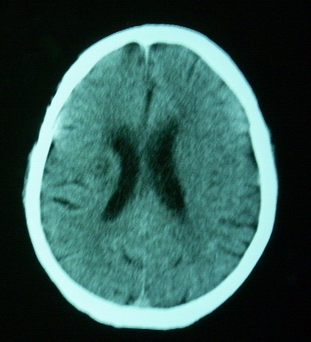

男,70岁,左侧肢体活动障碍口角向右侧歪斜2天,有高bp病史

pe:神情,能与之正常交流,吐字不清,180/90mmhg,双瞳孔无异常,左侧肢体肌力1级 b(+)

图中有个同心圆壮低密度影是ct伪影,见笑了。

1、右侧基底区及外囊区腔隙性脑梗塞。2、脑萎缩。

右基底节内囊前支区腔隙性脑梗塞,脑萎缩

支持右侧基底节区脑梗塞。

右侧基底区及外囊区腔隙性脑梗塞

右基底节区脑强隙 右基底节区低密度影密度太低 边界清 不会是2天的梗赛灶

2天左右的腔隙性脑梗死ct多难以发现 何况你的机器又差 很难显示 即使显示密度应该略低影

边缘模糊

支持腔梗。左内囊后肢亦有病灶